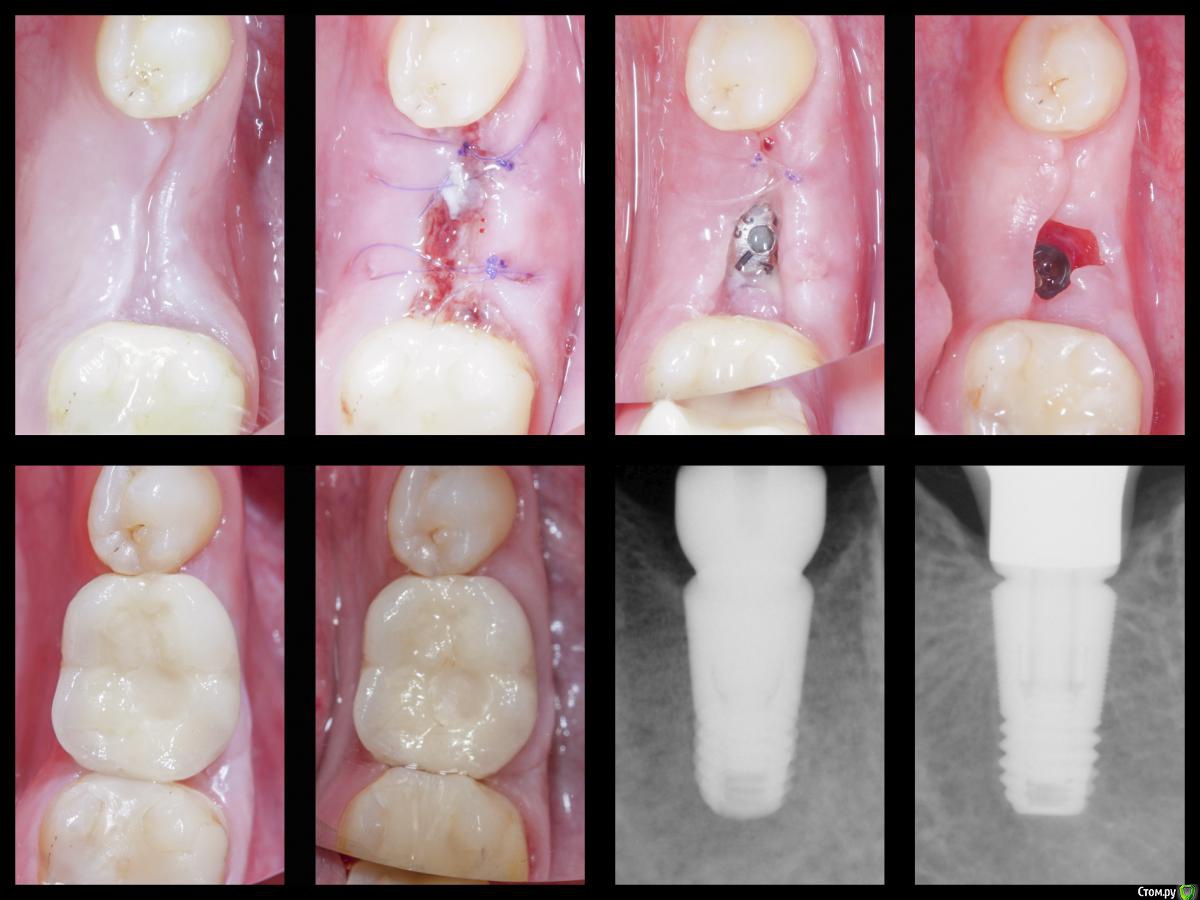

Я тут недавно удивлялся работе @AlexanderGudkov с "неправильным" протезированием и правильными результатами, сегодня показываю свой собственный "необъяснимый" опыт

Кроме рентгена приятно удивляет контур, который и выровнялся, и потолстел, особенно это заметно по прозрачным краям на этапе фдм.

Ещё, надо сказать, что тут мягкотканная работа получилась по заживлению вторичным натяжением, но случайно - просто прорезался один из швов.